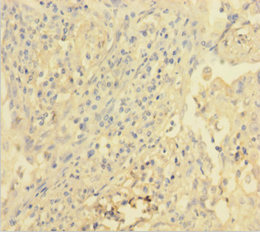

Immunohistochemistry of paraffin-embedded human liver cancer using CSB-PA07279A0Rb at dilution of 1:100

Immunohistochemistry of paraffin-embedded human lung cancer using CSB-PA07279A0Rb at dilution of 1:100